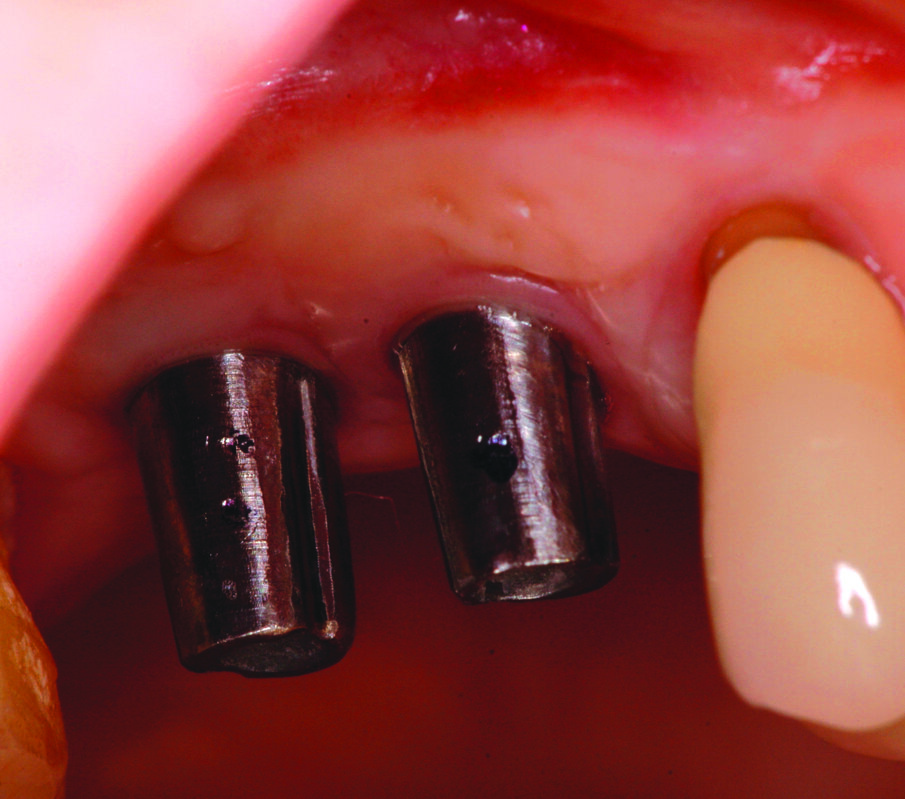

Una volta eseguito il disegno dell’antrostomia (Fig. 5), si procede al sollevamento della membrana con tecnica manuale (Figg. 6, 7) e all’iniziale inserimento di biomateriale granulare 0,5-1 mm (AlphaBio’s Graft, Alpha-Bio Tec, Israele). La corticale viene lasciata integra e aderente alla mucosa schneideriana in modo da diventare il futuro pavimento dell’antro (Fig. 8), anche per supportare il collasso della membrana durante il periodo di guarigione. A protezione della stessa è inserita una spugnetta di collagene equino (Condress, Smith&Nephew, UK). Contestualmente si procede con l’inserimento di due impianti autofilettanti SPI 3.75 x 13 mm (Alpha-Bio Tec, Israele) (Figg. 9, 10) e, al termine, viene ultimato il riempimento con biomateriale (Fig. 11). L’antrostomia viene poi coperta con una membrana riassorbibile 15 x 20 (AlphaBio’s Graft, Alpha-Bio Tec, Israele) e il lembo viene passivato e suturato con due linee di sutura 5-0: una a materassaio orizzontale e l’altra con punti staccati (Vicryl, Ethicon, USA) (Fig. 12). La paziente viene dimessa con la seguente terapia farmacologica: amoxicillina cpr 1 gr (1 cpr ogni 12h per 6 giorni), Prednisone cpr 25 mg (2 cpr per due giorni a scalare) per il controllo dell’edema post-operatorio e sciacqui con clorexidina 0.2% dal giorno successivo (1 sciacquo al giorno per 15 gg). Le suture sono rimosse a 15 giorni e la paziente è inserita in un programma di recall a cinque settimane per gestire eventuali complicanze durante la maturazione dell’innesto. Viene eseguito il secondo tempo chirurgico dopo 6 mesi e, verificata l’avvenuta osteointegrazione degli impianti, vengono rilevate le impronte e il caso è finalizzato con due corone unite in metallo ceramica (Figg. 13-15). Al termine della riabilitazione, visto il buon mantenimento igienico, la paziente viene inserita in un programma di follow-up a sei mesi (Figg. 16, 17).

Fig. 9_Fasi dell’osteotomia implantare.

Fig. 10_Particolare dell’iniziale riempimento del seno mascellare e dell’inserimento implantare.